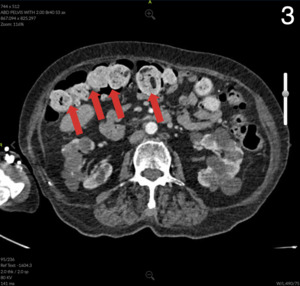

Computed Tomography (CT) of the abdomen and pelvis showed colonic wall thickening particularly in the pelvis close to the vaginal vault. A colonoscopy revealed a severe kink that could not be crossed in the sigmoid colon and extensive diverticular disease.

Pathology of the colonic portion of colovaginal fistula revealed severe acute on chronic diverticulitis with stricture, perforation, and fibrinous serositis with adhesions consistent with clinical history of colovaginal fistula negative for dysplasia or malignancy. The anastomotic donuts were benign and viable colonic mucosa was negative for dysplasia or malignancy. Review of microbiology of the vaginal canal revealed detection of only normal vaginal flora that was negative for G. vaginalis, T. vaginalis, N. gonorrhoeae, C. trachomatis, and C. albincans.